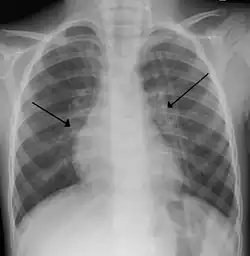

The diagnosis is typically made by a provider through clinical history and physical exam. Chest X-ray is sometimes useful to exclude bacterial pneumonia, but not indicated in routine cases.[1] Chest x-ray may also be useful in people with impending respiratory failure.[15] Additional testing such as blood cultures, complete blood count, and electrolyte analyses are not recommended for routine use although may be useful in children with multiple comorbidities or signs of sepsis or pneumonia.[8][15] Electrolyte analyses may be performed if there is concern for dehydration.[1]